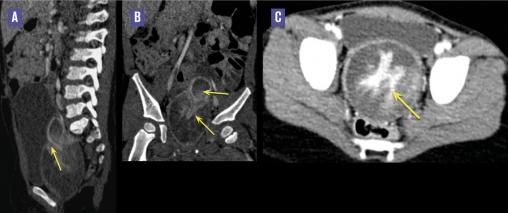

Cette enfant de 2 ans, en bon état général, était adressée pour une masse prolabée à travers l’hymen évoluant depuis 4 mois. L’examen urogénital montrait une masse extériorisée perforé sans envahissement local visible. Un scanner abdomino-pelvien (v. figure ) révélait de volumineuses masses tissulaires hétérogènes confluentes, de contours irréguliers, comblant la lumière vaginale trop dilatée, s’étendant à travers le col utérin vers la lumière utérine qui était comblée et responsable d’un aspect aminci du myomètre. Aucune localisation secondaire à distance n’était notée. Une vaginoscopie montrait plusieurs formations polyploïdes. Une exérèse de 12 formations était alors réalisée. L’étude histologique était en faveur d’un rhabdomyosarcome botryoïde classé risque standard type C devant l’âge de la patiente, la taille, le site favorable, l’absence d’adénopathies et le type botryoïde (embryonnaire). L’enfant est actuellement sous chimiothérapie.